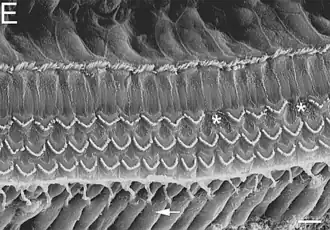

Células ciliadas dentro de la cóclea.

Células ciliadas internas y externas del Órgano de Corti. Vista de superficie apical con estereocilios.

Estereocilias de células externas del órgano de Corti.

Estas tres cámaras están separadas por dos membranas: la membrana de Reissner, entre la rampa vestibular y la rampa media o coclear; y la membrana basilar, entre la rampa media o coclear y la rampa timpánica. Es en la membrana basilar donde descansa el órgano de Corti con las células ciliadas (que son los receptores auditivos). El eje en torno al cual se enrolla la cóclea se conoce como modiolo o columela. Junto a él está el ganglio espiral de Corti de donde parte el nervio auditivo (VIII par craneal).[5]